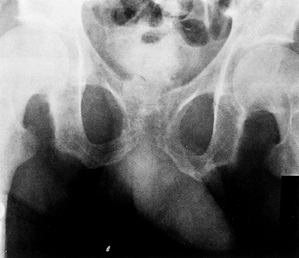

present. Bowing of the long bones and genu valgum are common.

can be seen at the terminal tufts of the distal phalanges, the

symphysis pubis (Fig. 180.28), and the end of

the clavicle. Metaphyseal resorption of bone leads to widened physes

and slipped capital femoral epiphysis (SCFE; see Chapter 172) (Fig. 180.29). Disturbance of the proximal lateral tibial physis with associated genu valgum has been described (161).

![]() |

|

Figure 180.28. Resorption of the pubis due to renal osteodystrophy.